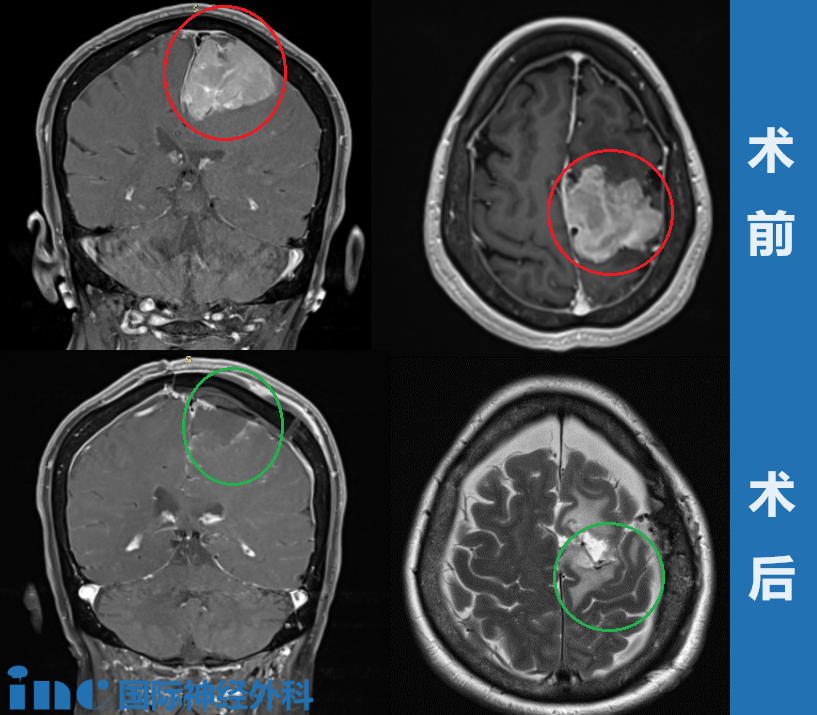

術(shù)前影像資料:左側(cè)大腦鐮旁巨大腦膜瘤,鈣化和瘤周壓迫、水腫效應(yīng)明顯。

手術(shù)過程:左側(cè)額葉到額頂葉旁矢狀面的成骨性環(huán)鋸術(shù)和顯微外科腦膜瘤切除術(shù);自體骨膜移植的硬腦膜成形術(shù)。

王女士的手術(shù)情況成功,腫瘤全切、矢狀竇成功重建、運(yùn)動(dòng)功能區(qū)無損傷,預(yù)后無并發(fā)癥、沒有復(fù)發(fā)。

術(shù)后影像資料:腫瘤肉眼下全切,可見局部組織缺陷,水腫效應(yīng)存在,被壓迫正常腦組織緩慢復(fù)位。

大腦鐮旁較大腦膜瘤——術(shù)前術(shù)后